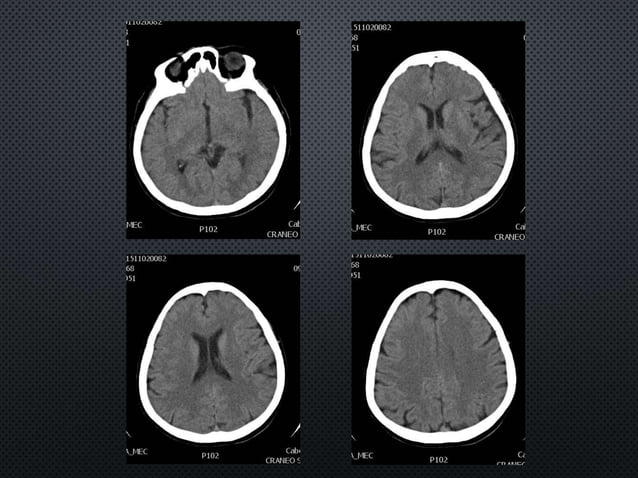

El diagnóstico se confirma con neuroimágenes, principalmente la tomografía.

![infartocerebelosotac.jpeg [Neurocirugía Contemporánea ISSN 19882661]](http://www.neurocirugiacontemporanea.com/lib/exe/fetch.php?cache=&media=infartocerebelosotac.jpeg)